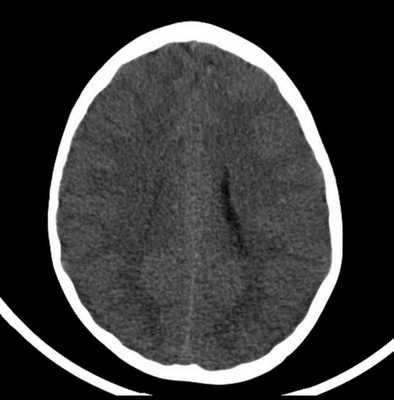

На русунках 2 и 3 показаны типичные изменения, обнаруживаемые при КТ.

Рисунок 2 | 9-тилетний мальчик, переживший ДТП. КТ, сделанная в день травмы, показала несколько гиперденсных фокусов в левой лобной доле.

Рисунок 3 | КТ-сканы демонстрируют несколько гиперденсных очагов, наиболее крупный - в левой лобной доле. Признаки отека вещества мозга.

КТ-картина диффузного аксонального поражения мозга характеризуется увеличением объема мозга, в результате которого под сдавлением находятся боковые и III желудочки, субарахноидальные конвекситальные пространства, а также цистерны основания мозга. Нередко выявляют наличие мелкоочаговых геморрагий в белом веществе полушарий мозга, мозолистом теле, подкорковых и стволовых структурах.

Рис. 2 и 3 демонстрируют типичные изменения, обнаруживаемые при КТ.

Рисунок 2.

Рисунок 3.